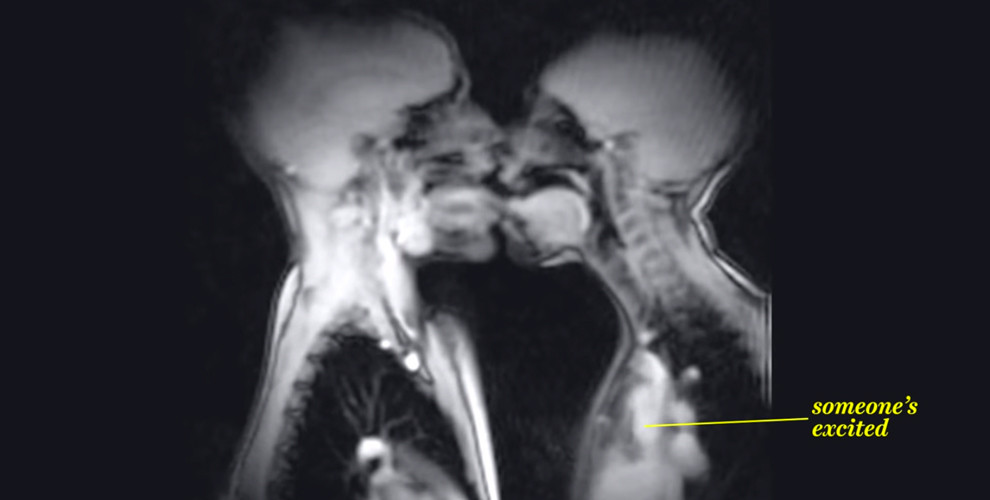

Otsikkokuvassamme on kuvattuna suutelevat ihmiset MRI-laitteella, eli kuvannettuna ydinmagneettiseen resonanssiin perustuvalla mageettikuvauslaitteella. Normaalisti sairaanhoidossa käytettävä laite on erinomainen paitsi siksi, että siinä ei tutkittavaan potilaaseen ei jouduta kohdistamaan röntgensäteilyä, vaan hänen sisuskalunsa saadaan näkyviin veden sisältämien vety-ytimien magneettikentässä lähettämää radiosignaalia havaitsemalla. Ja verrattuna normaaliin röntgenkuvaan on MRI erinomainen myös siksi, että sen avulla pystytään kuvantamaan videoita – siis ihmiskehoa toiminnassa.

Vox.com -nettisivu on tehnyt jännittävän koosteen (joka on myös alla) MRI-kuvista, joissa taitsi suudellaan, niin myös näytetään muita elintoimintoja. On oikeastaan häkellyttävää nähdä mitä sisällämme tapahtuu ja miten elimemme toimivat.